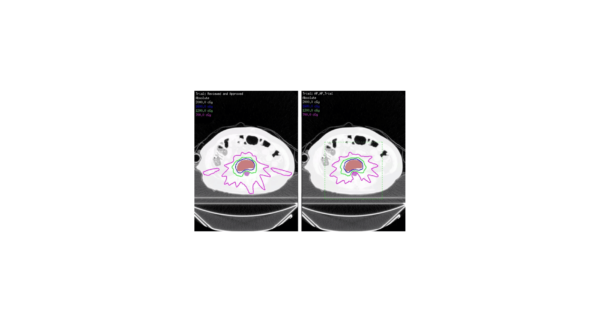

Функция Автоматического планирования оптимизирует объем исследуемого объекта и защиту чувствительных органов. Уменьшает необходимость многократной проверки плана врачом и дозиметристом и работает в фоновом режиме, освобождая время для других задач.